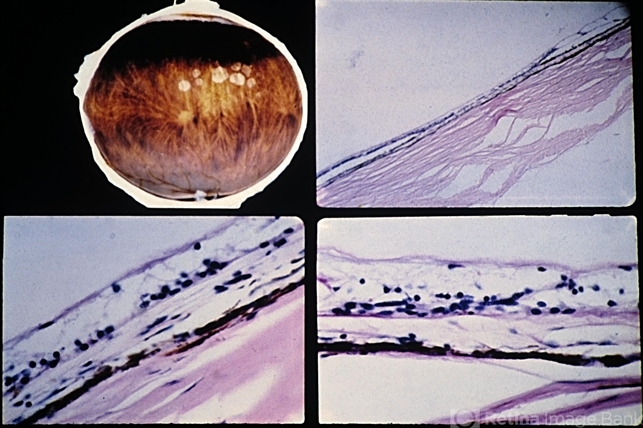

- choriocapillaris, retinal pigment epithelium, Bruch's membrane

- Paving-stone degeneration. There is loss of the choriocapillaris, RPE, and outer retinal layers. The thinned inner nuclear layer of the retina rests against Bruch's membrane, and there is no reparative proliferation. Adjacent RPE is hypertrophic.